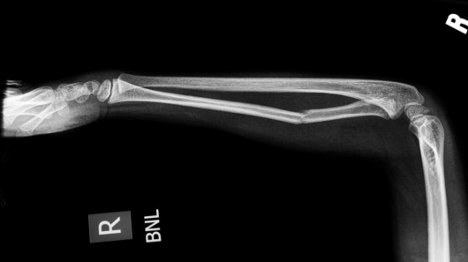

对于那些不幸的人来说,您一生中骨折了一两骨,您会知道那些骨头愈合所花费的漫长而痛苦的时间。经历了这一磨难的孩子可能还记得所有的同学都急于签署演员。

情况不再是这种情况。佐治亚大学的一组研究人员创建了一个“裂缝油灰”,以减少骨头骨折的愈合时间。

这种新的断裂愈合果皮可将骨骼愈合的时间从几个月缩短到几周,而受伤的人能够在几天之内起床并走动。研究人员使用了成年干细胞,因为它们产生了有助于骨形成的酶。在最初的开发阶段,对实验室大鼠进行了测试。将大鼠注入裂缝部位,并使用稳定装置将骨骼固定在适当的位置。大鼠在两周内显示出完全恢复的迹象。

裂缝油腻的主要目的是帮助那些更有可能使骨头骨折并受到医院病床的日子的影响的士兵。该油灰是用于对大型动物进行测试的开发,然后转移到美国国防部,使其适合人类使用。

裂缝油灰只是科学家研究骨骼愈合过程的可能方法之一。有些包括完全更换骨折的骨头,而另一些类似于腻子,但使用不同的材料来治愈骨骼。下图显示了德克萨斯大学使用基于硅胶聚合物的油腻的果皮来治愈骨骼的尝试。